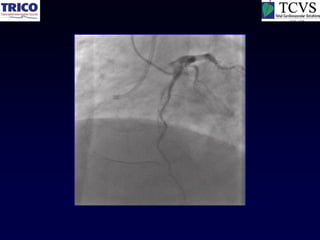

RCA CTO